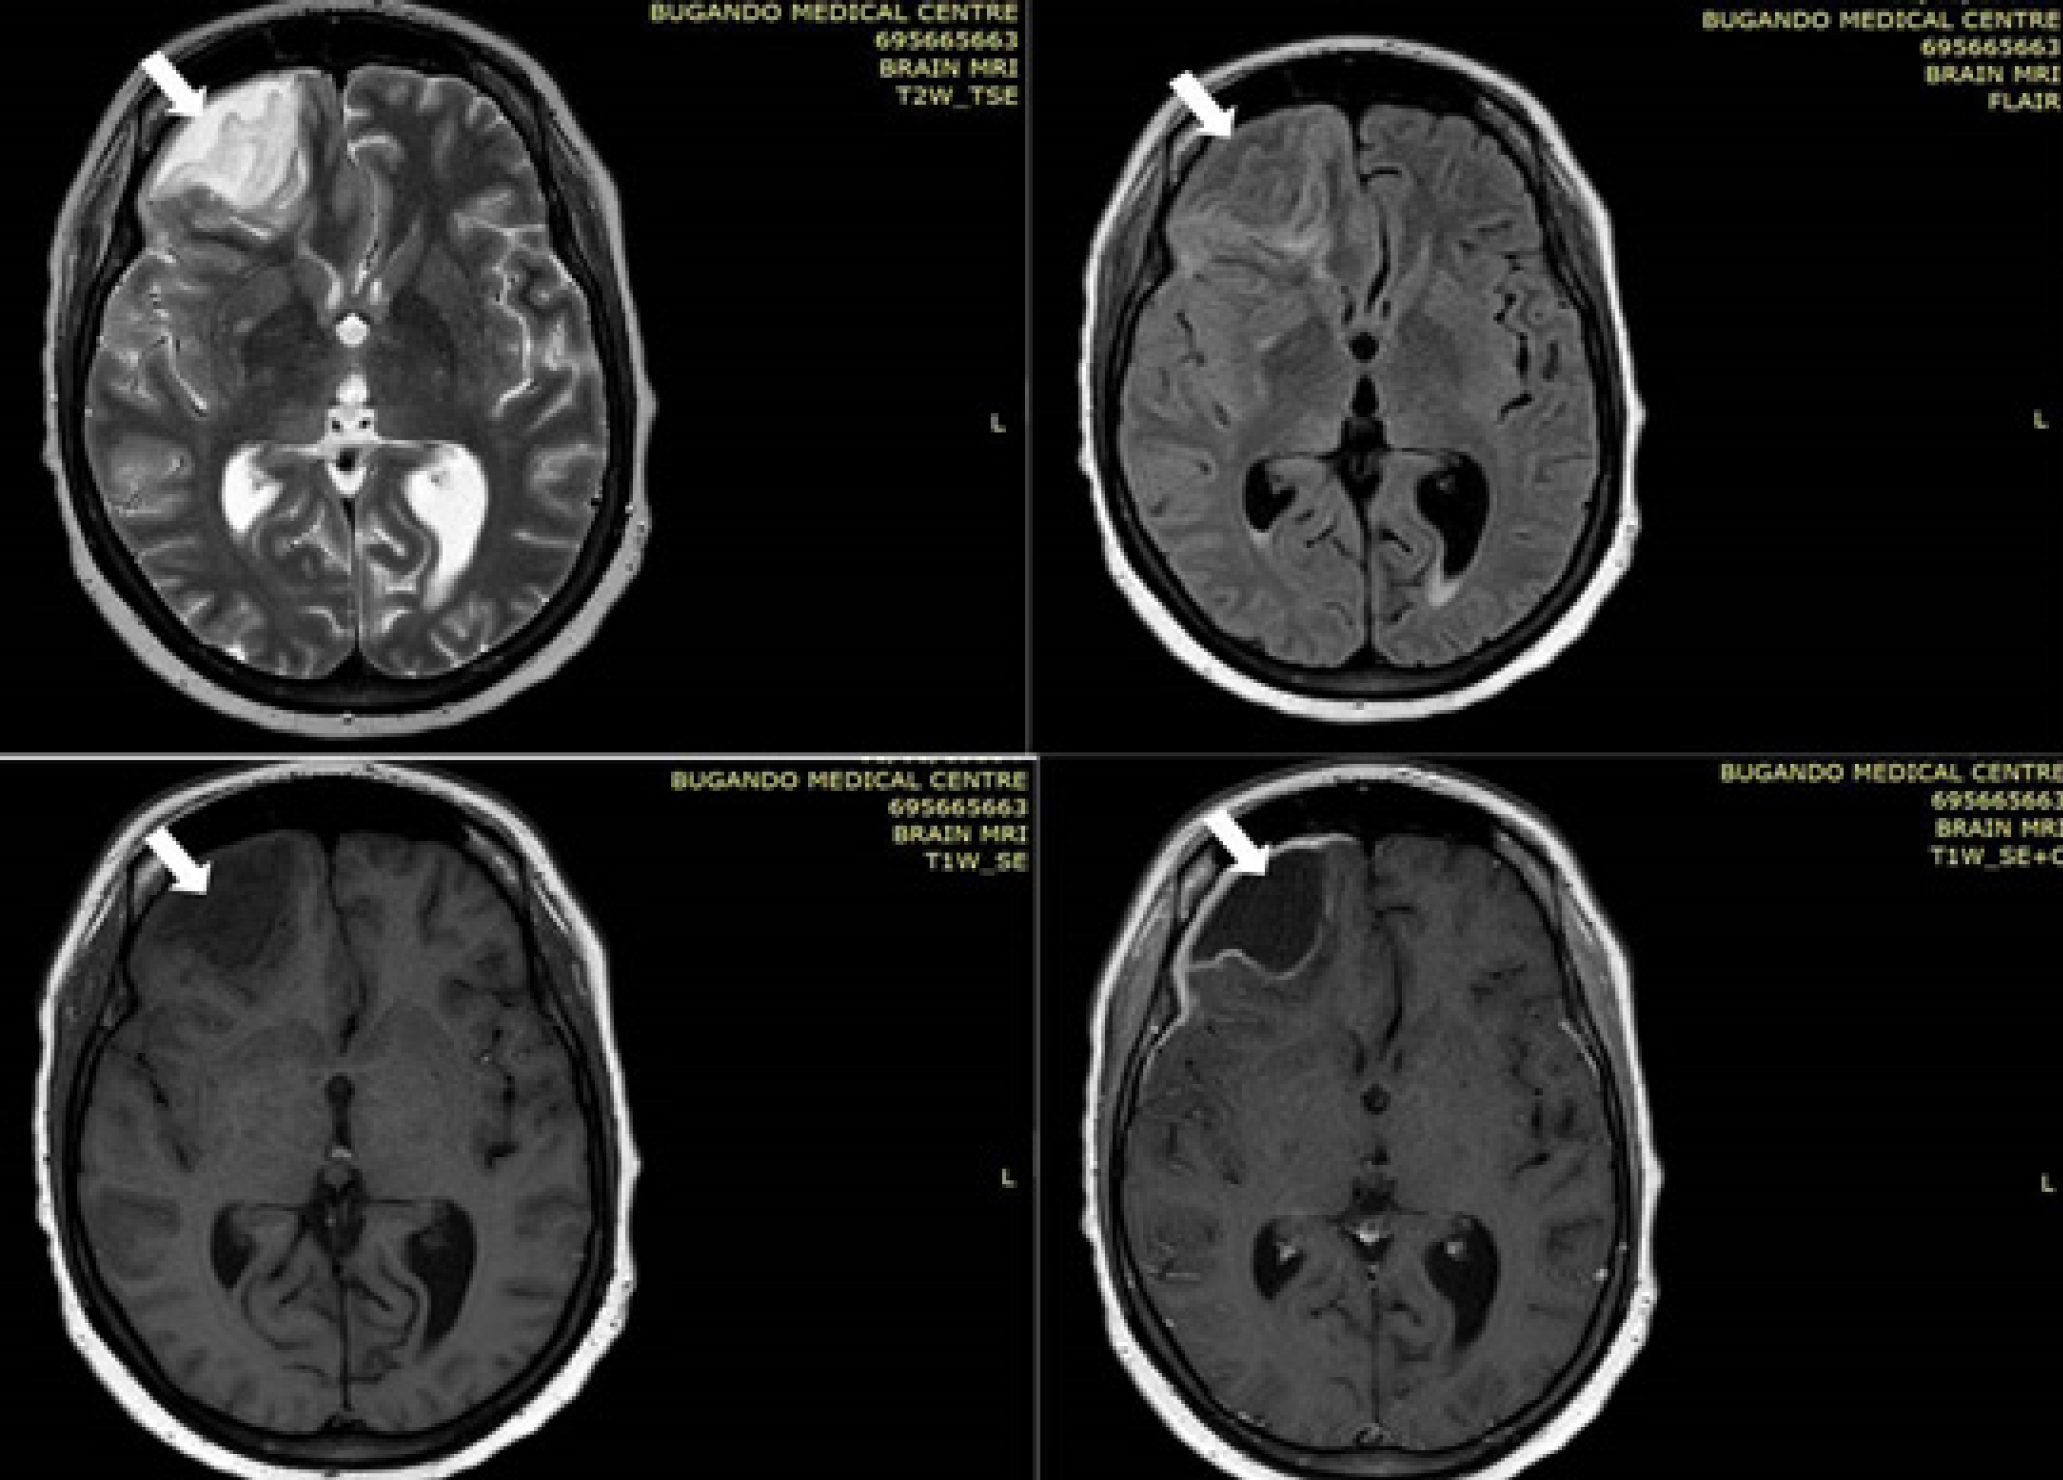

Case studies Presentation: This report presents four distinct cases of dental issues leading to severe complications, including brain abscess, empyema thoracis, Ludwig’s angina, and maternal sepsis. A multidisciplinary approach was employed in managing these cases, tailoring interventions based on individual patient needs. While three cases resulted in positive maternal outcomes, one case experienced poor outcomes due to Ludwig’s angina. Unfortunately, perinatal deaths occurred in three cases, attributed to preterm delivery and intrauterine foetal demise, with only one case yielding a favourable perinatal outcome.